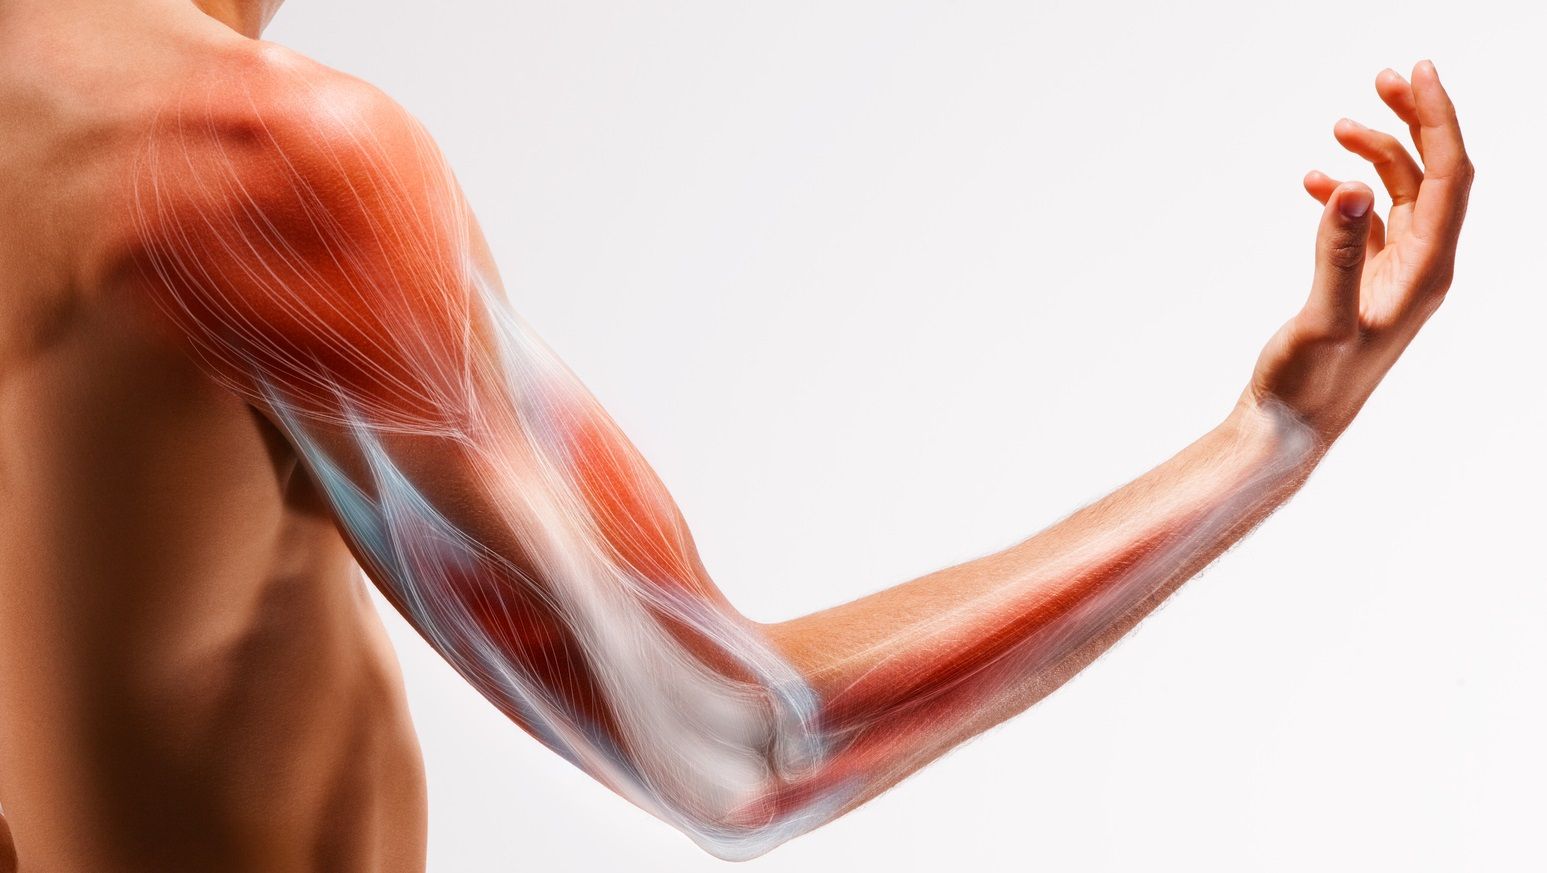

Диаграммы и схемы движения в суставах человека